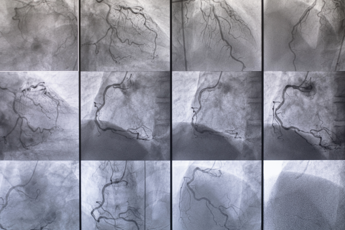

(Adnkronos) – Dietro quasi ogni patologia cronica si trova o si affianca una malattia vascolare. Facili da prevenire, gravi fino all’amputazione o alla perdita della vita se trascurate, le malattie vascolari – secondo gli esperti – colpiranno un quarto della popolazione italiana. Interessano arterie, vene e linfatici e sono responsabili del 22% delle morti in Italia e fanno perdere 10mila arti all’anno. "Bisogna affrontarle con la stessa determinazione di infarti, ictus e tumori – spiega il presidente della Società italiana di chirurgia vascolare e endovascolare (Sicve) Gaetano Lanza – e richiedono un approccio sistemico di prevenzione e governance". Da qui la nascita della Consulta per le Malattie Vascolari che unisce le grandi Società scientifiche e gode del patrocinio di Agenas e Istituto superiore di sanità. L'annuncio questa mattina in apertura di Welfair 2024, la Fiera del fare sanità, dal 5 al 7 novembre alla Fiera Roma. "Ischemie degli arti, aneurismi, ostruzioni carotidee, aterosclerosi, flebo e linfopatie e tumori vascolari sono tra le più importanti cause di mortalità e invalidità nel nostro Paese – spiega Lanza – E sono responsabili del 22% delle morti, subito dopo infarto miocardico (28%) e ictus cerebrale (25%). Oltretutto, le malattie vascolari risultano in costante aumento per l'incremento nella popolazione dell'età media e di diversi fattori di rischio quali ipertensione arteriosa, diabete mellito, dislipidemie, obesità, fumo, inquinamento, comportamenti e stili di vita non corretti, alimentazione errata e inoltre per predisposizioni genetiche". "Una peculiarità della malattia arteriosa degli arti inferiori, per esempio, è di rappresentare un importante fattore di rischio per patologie arteriose in altri distretti corporei: i pazienti affetti da arteriopatia periferica hanno un rischio molto elevato di presentare patologia coronarica o carotidea, con un corrispondente aumento del rischio di infarti ed ictus" sottolinea Angelo Santoliquido presidente del Collegio italiano di flebologia (Cif). "Accanto a queste ci sono poi le flebopatie croniche e acute, alcune delle quali responsabili di Embolia Polmonare a rischio di morte improvvisa" aggiunge Roberto Di Mitri, presidente della Società italiana di flebologia. Sono, inoltre, sempre più frequenti in una popolazione che invecchia, fragile e polipatologica: un bacino di "oltre 4 milioni di persone che vivono sole, 800.000 persone in cure palliative, e almeno 650.000 con disabilità – precisa Claudio Novali, primario emerito di Chirurgia Vascolare Ospedale di Cuneo e presidente Associazione pazienti malattie vascolari titoccotoccati Aps – È in questo bacino che la malattia aterosclerotica agli arti inferiori (Aocp) – che colpisce oltre il 20% dei pazienti con più di 70 anni – può sviluppare, quando non correttamente curata l’ischemia critica agli arti inferiori, responsabile nel 50 % di questi pazienti delle amputazioni: oltre 11mila ogni anno in Italia. Fra l’altro, un paziente amputato ha un rischio maggiore di incorrere a complicanze cardiache, cerebrali e di mortalità. I dati in nostro possesso ci dicono che oltre il 50% dei pazienti amputati non hanno avuto un percorso di presa in carico corretta e tempisticamente efficiente". È per far fronte a questo scenario quanto mai complesso e urgente che nasce la Consulta delle Società scientifiche e Associazioni pazienti per le malattie vascolari. La Consulta unisce alcune tra le più importanti associazioni scientifiche del settore: la Società italiana di chirurgia vascolare endovascolare (Sicve), l’Associazione flebologica italiana (Afi); il Collegio italiano di flebologia (Cif); la Società italiana di flebologia (Sif); la Società di flebolinfologia (Sifl); la Società per lo studio delle anomalie vascolari (Sisav); l’Associazione pazienti prevenzione malattie vascolari (Ttt). "In sintesi, la Consulta – spiega Lanza – nasce per portare le malattie vascolari al centro dell’attenzione e della pianificazione sanitaria. Parliamo alle Istituzioni e ai decisori sanitarie parliamo ai cittadini". "Abbiamo bisogno di programmi di educazione, prevenzione, diagnosi, cura e presa in carico dei pazienti per ridurre un impatto sociale ed economico che, solo per la Malattia venosa cronica (Mcv) a titolo d’esempio, interessa il 40% della popolazione generale e incide per il 2% dell’intera spesa sanitaria" interviene Maurizio Ronconi, direttore S.C. Chirurgia generale ASST Spedali Civili di Brescia e Presidente Associazione Flebologica Italiana. “Nel campo estremamente delicato delle anomalie vascolari – malattie rare che colpiscono il 4-10% della popolazione, congenite e particolarmente invalidanti nell’età fragile dell’adolescenza – l’Italia oggi ha accumulato una grande competenza chirurgica – evidenzia Francesco Stillo, ex presidente Sisav – Negli anni ‘90, l’80 % dei pazienti in Francia per queste patologie proveniva dall’Italia. Dopo grandi investimenti fatti dai medici per imparare e perfezionare le tecniche, questa percentuale è scesa al 5%. Oggi rischiamo di perdere il patrimonio di conoscenze accumulate, perché le uniche strutture rimaste sono cliniche convenzionate mentre le liste di attesa si allungano. Immaginiamo un giovane adolescente in uno dei momenti più delicati della sua vita, costretto ad aspettare mesi per ricevere un trattamento per una malformazione che è sia fisicamente invalidante che psicologicamente molto difficile da accettare. Abbiamo bisogno di investire in almeno 3 Centri Specializzati pubblici sul territorio nazionale. Il punto di partenza devono essere le Linee guida che abbiamo realizzato con l’approvazione del ministero della Salute nel 2021". Ci sono poi i "linfedemi cronici degli arti, patologie altamente invalidanti anche in pazienti giovani" conclude Maurizio Pagano, presidente della Societá italiana di flebolinfologia.  —salutewebinfo@adnkronos.com (Web Info)